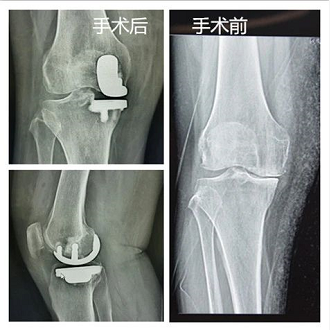

单髁置换影像

膝关节单髁置换术是一项微创、精准的手术技术,只置换病损部位,替代病变的关节软骨、半月板而保留膝关节正常的韧带和其他组织的一种微创关节置换手术。单髁置换术由于膝关节的韧带得到保留,患者术后的膝关节活动度和本体感觉更好,更容易感知膝关节运动过程中的力量变化、位置变化,感觉术后膝关节和正常关节并无明显差异,在经过康复训练之后,更容易“遗忘”这次手术,运动更加协调与自如。

全膝置换影像

全膝关节置换手术作为一种非常成熟的手术,主要是将病变的表面关节软骨切除,然后利用金属来代替这个关节表面,进行人工置换,以此来达到恢复膝关节功能的目的。在全膝关节置换手术后的患者一般疼痛感会比较强烈,手术后想要有更好的效果,除了手术成功,术后的康复治疗也至关重要。我们遵循“快优康复”的原则,要求患者手术当天下地站立,术后就开始进行康复训练,加速恢复。术后的康复训练可以加快血液循环,让炎性介质很快排出体外,过后患者的疼痛就非常轻。